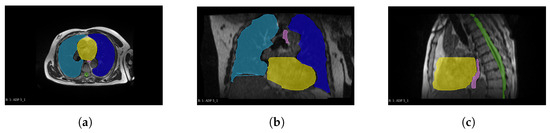

2.2. Preprocessing